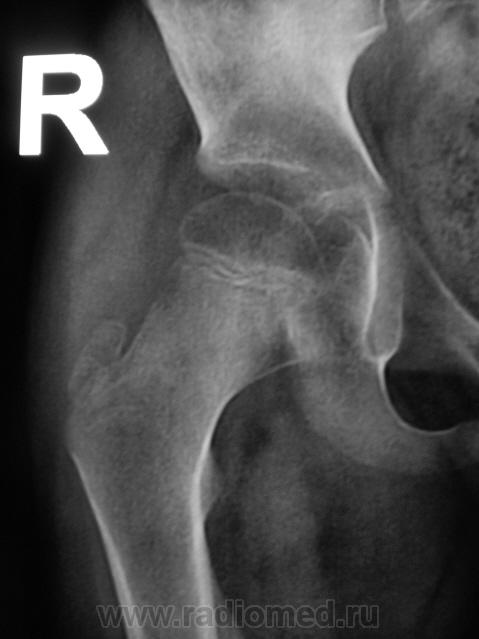

Пациент направлен на конрольное рентгенологическое исследование средней трети бедренной кости с целью оценки консолидации. Ранее - первичный снимок пациент был направлен на рентгенографию средней трети бедра, что и было сделано. Но, при производстве "контроля" рентгенолаборанты захватили тазобедренный сустав в прямой проекции, и возникли неясные сомнения по поводу головки, да и вообще...

Какой-то «змей 2х-головый» и впадина не слава богу. Надо или детских рентгенологов ждать или вторую проекцию делать.

Сама головка не нравится, особенно её нижне-медиальный отдел.

Согласна, что-то и меня в глазах головка бедра двоиться.

Пожалейте ребенка, не надо томографировать. Все укладывается в норму. Просто головка еще маленькая, а медиально - это шеечная шпора. Уж если не верите, снимите оба сустава одновременно.

Вероятно остеопороз головки от функционального щажения, разрушений не видно, капсула (мягкие ткани) параартикулярно - в норме...

А в нижней половине вертлужной впадины всё ОК?

Плохо ножечка в тазобедренном ходит, вот и боковая укладка, выполнена на "раскоряку" лаборантами не просто так, не отводит ноженьку пациент.

Конечно не отводит, потому что контрактура сформировалась за время иммобилизации. У нас все дети после таких переломов госпитализируются на разработку.

Интересная дискуссия. Жаль с опозданием увидел (однако же, много времени уходит, пока всё на сайте просмотришь). На мой взгляд, патологии головки нет, без фрагментации, проекционно пересекается с тенью обызвествляемого Y-хряща. Под головкой медиально, несомненно, есть остеопороз, придающий нечеткость картине. Впрочем, регионарный остеопороз имеет место вследствие закономерной атрофии после иммобилизации. Сюда же наслаивается субстрат т.н. фигуры серпа, еще не оформленный. Впадина нормальная. Кость срослась - замечательно, всем бы такие результаты. Реабилитация обязательна.